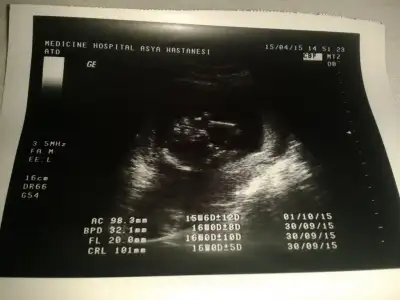

dr soylemeden siz gorun genital nub teorisi ( bebegin cinsiyeti)

Benim minik ordegime de tahmin yapar misiniz ablalari?

Kızlar ben de koysam yorum yapabilir misiniz. .Allah nasip ederse İkizlerim olacak.biri kız ama diğeri göstermedi kendini..Haftaya 16. Hafta dolacak o zaman gideceğim ama çok merak ediyorum..